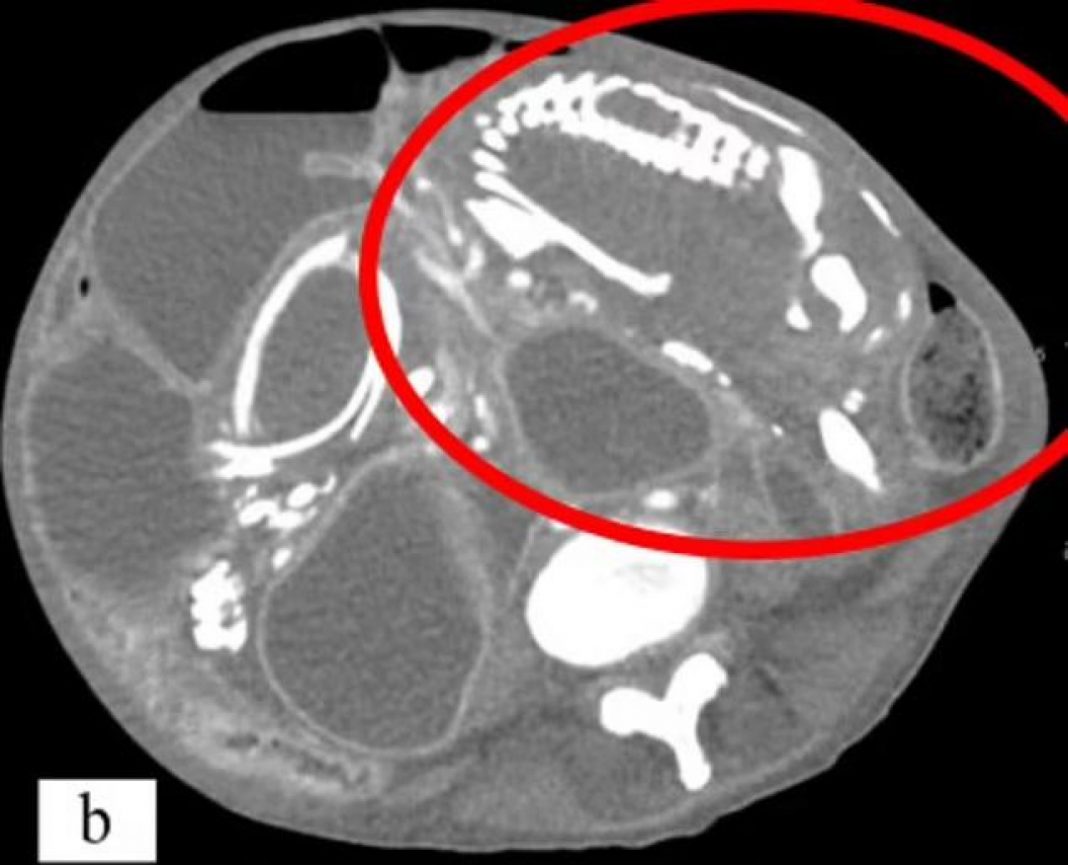

Kad je stigla u SAD, odvedena je na CT koji je otkrio opstrukciju tankog crijeva i kompresiju velikih vena, kao i masu unutar abdomena koja je bila otprilike 15 puta 20 centimetara i sadržavala je kostur.